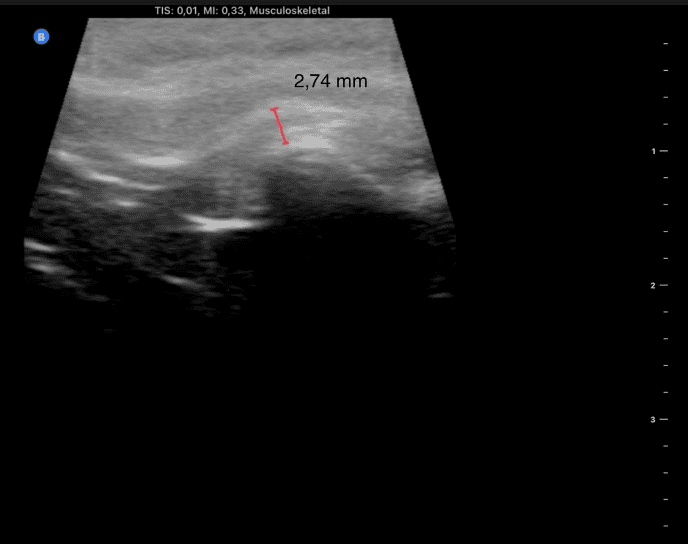

Ecografia ATM. Articulația văzută în mișcare

Ecografia articulației temporo-mandibulare permite evaluarea dinamică a articulației în timpul deschiderii și închiderii gurii. Este o metodă nedureroasă și poate fi repetată pentru monitorizare.

Prin ecografie se pot observa:

-inflamația locală

-poziția discului articular

-asimetria între cele două articulații

-modul real în care se mișcă maxilarul